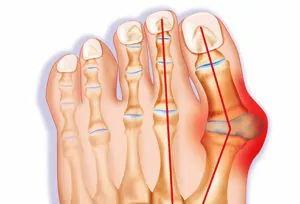

Bunions

- What it is: Also called “hallux valgus”, bunions occur when the joint at the base of the big toe becomes stretched out and possibly subluxed, resulting in your big toe pointing in towards your other toes.

- Common Symptoms: The joint of your big toe may be swollen, painful, and the muscles of the big toe may be weak.

- Treatment: Rest the big toe from aggravating activities like heel raises and doing activities on your toes (yes, that means taking a break from pointe shoes). Then work on mobilizing the joint (restoring the range of motion) and strengthening the big toe muscles.

- Prevention Tips: Avoid wearing narrow toed shoes or excessively tight footwear for prolonged periods of time.